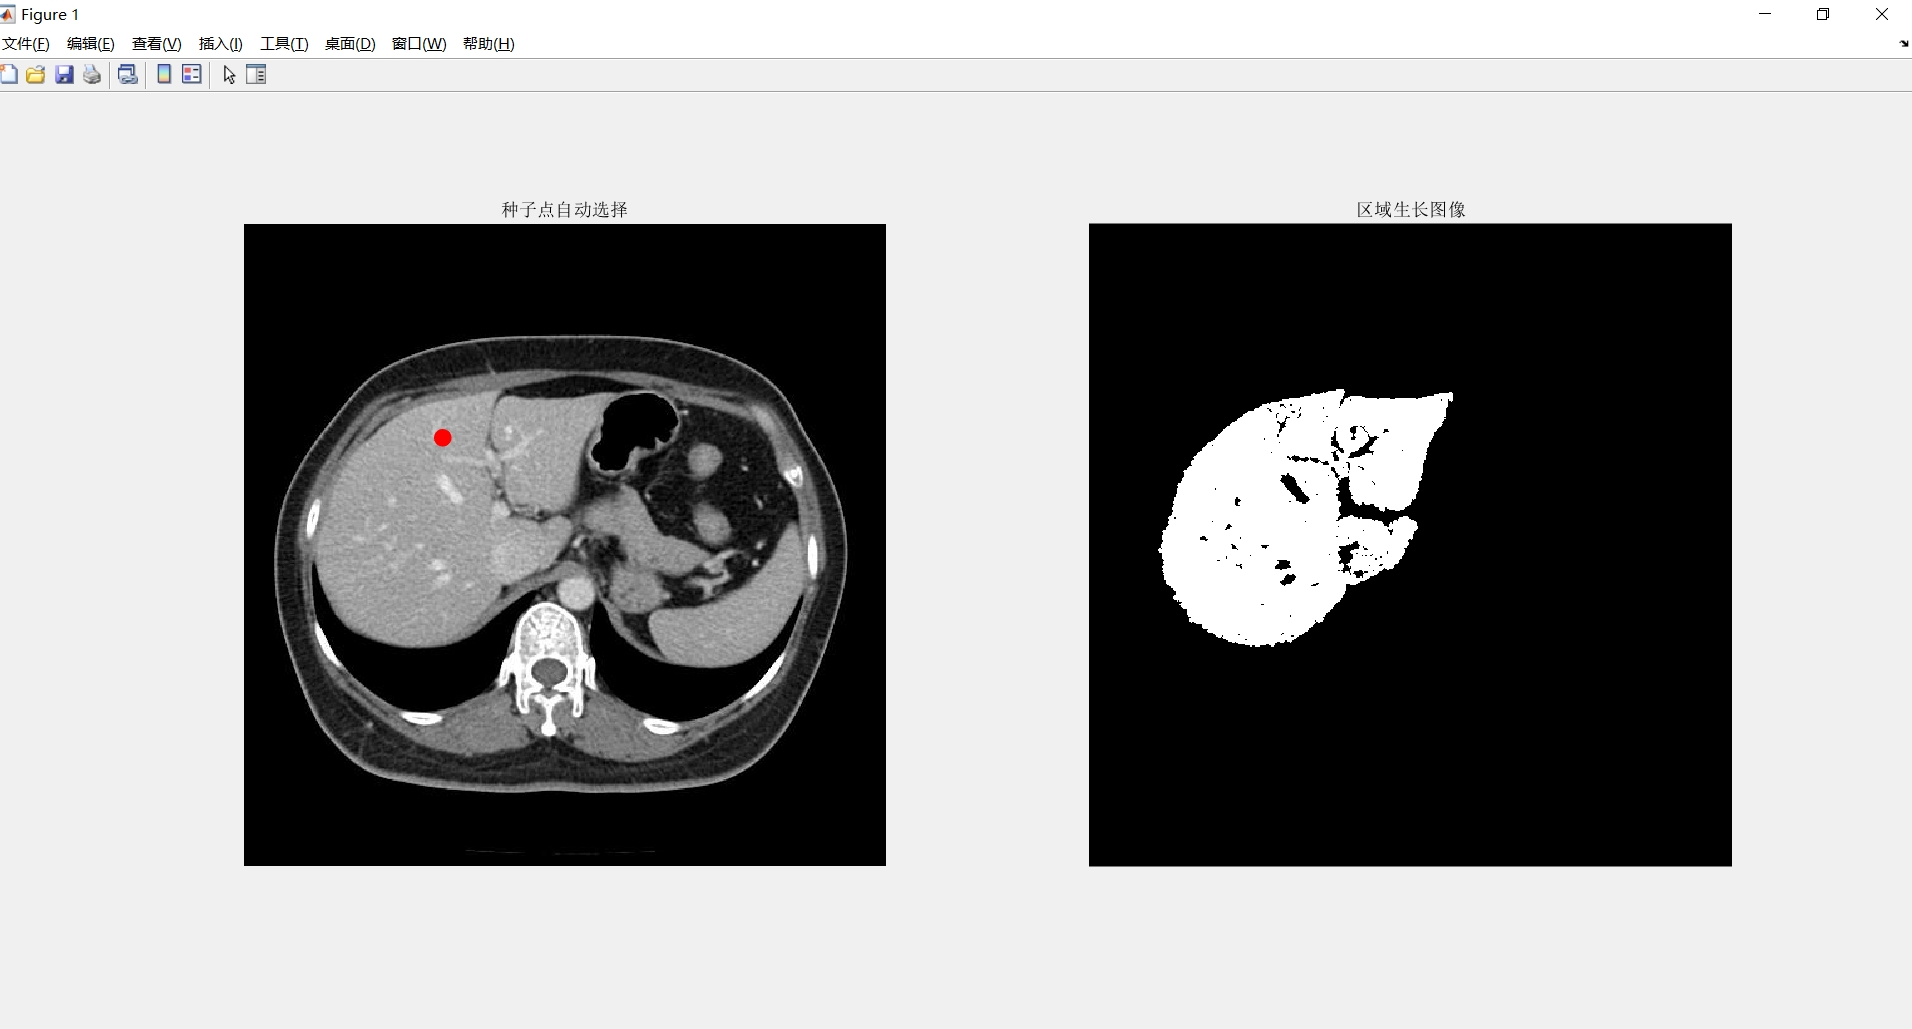

区域生长:它是根据事先定义的准则将像素或者子区域聚合成更大区域的过程。

其基本思想是从一组生长点开始(生长点可以是单个像素,也可以是某个小区域),将与该生长点性质相似的相邻像素或者区域与生长点合并。

然后将这些新像素当作新的生长点,继续上面的操作,一直重复此过程,直到没有满足条件的像素可被包括进来,此时就表示生长点已经不能生长,这样一个区域就生长成了。

生长点和相似区域的相似性判断依据可以是灰度值、纹理、颜色等图像信息。